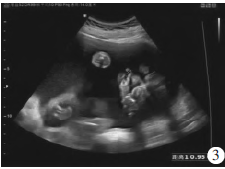

胎儿左眼距1.2 cm,右眼距1.2 cm,眼距1 cm(图2)。胎儿上唇中部唇腭回声缺失约0.9 cm(图3)。胎儿双肺显示不清,部分肝脏进入左侧胸腔,右移(图4)。胎儿右侧足底平面和小腿骨骼长轴切面可在同一切面内显示,右侧拇趾短与第2趾间距增大(图5)。超声诊断:①单胎,中孕,存活儿;②胎儿全前脑畸形;③胎儿全前脑面容(正中唇腭裂、眼距过近);④胎儿右足内翻合并拇趾短、草鞋脚;⑤胎儿左侧膈疝;⑥脐带胎盘入口处囊肿;⑦羊水过多。

图3胎儿上唇超声表现